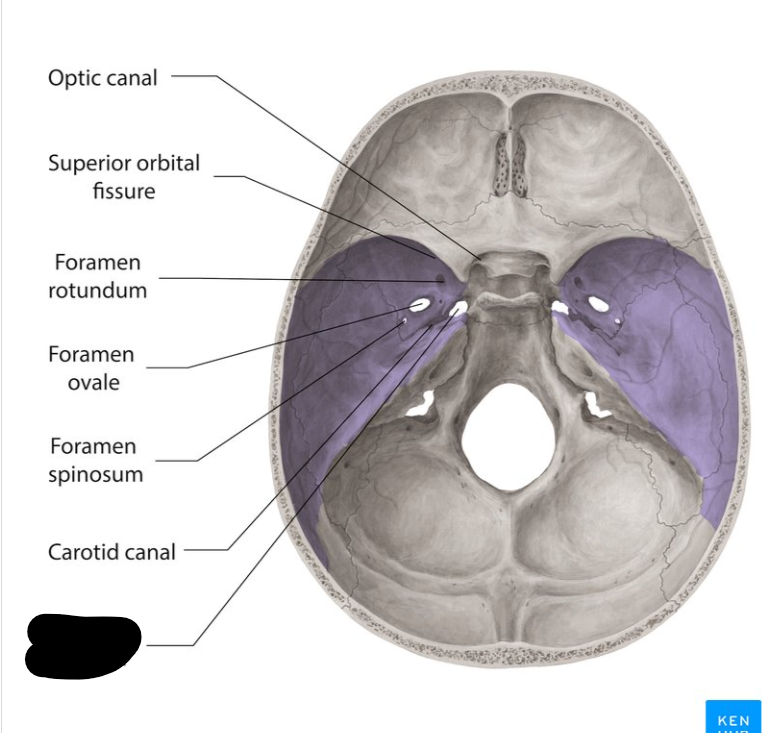

Middle cranial fossa

Foramen rotandum

Foramen ovale

Foramen lacerum

Foramen spinosum

Superior orbital fissure

Optic canal

Carotid canal